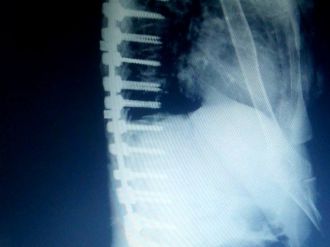

Edremit’te Bir Hastaya Erimeyen Platinden Omurga Yapıldı